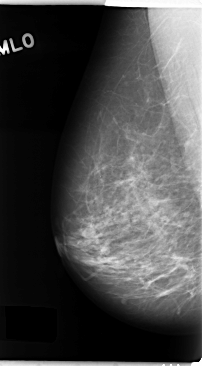

C_0137_1.RIGHT_MLO

RIGHT_CC LINES 4744 PIXELS_PER_LINE 2600 BITS_PER_PIXEL 12 RESOLUTION 50 NON_OVERLAY

RIGHT_MLO LINES 4752 PIXELS_PER_LINE 2624 BITS_PER_PIXEL 12 RESOLUTION 50 NON_OVERLAY